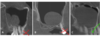

What is CBCT FoV and how can it change?

A

Visible Field of View

• Can be adjustable

• Full FoV = nearly full skull (used for ortho)

• Medium / standard = both arches and TMJ

• Small FoV = one arch or quadrant

Want to limit the field size to the smallest volume that can accomodate the region of interest